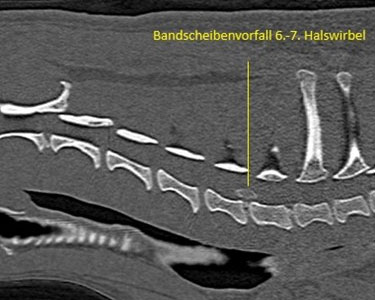

Bandscheibenvorfall Halswirbelsäule (französische Bulldogge):